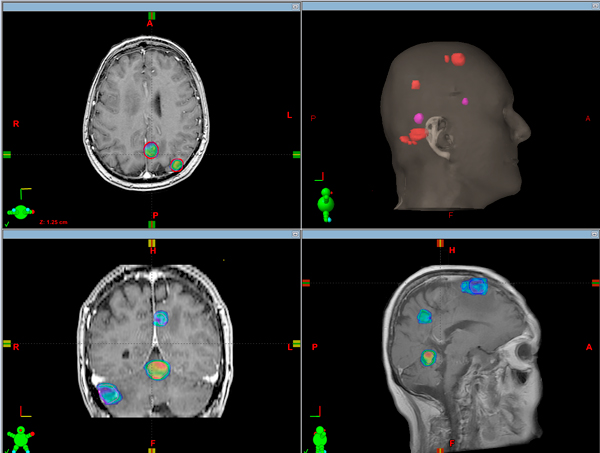

La tecnología recientemente adquirida por nuestro Centro ofrece nuevas opciones de tratamiento en ciertos tumores y metástasis cerebrales. La particular capacidad de combinar las técnicas de RapidArc con la Radioterapia Guiada por Imágenes (IGRT) facilita la realización de tratamientos de Radiocirugía Estereotáctica sin la necesidad de colocar un marco rígido fijo al cráneo del paciente y acortar sustancialmente el tiempo de la aplicación.

El hecho de no necesitar un marco fijado al cráneo, posibilita aumentar las indicaciones de la Radiocirugía en tratamientos de tumores que requieren varias aplicaciones de radioterapia. Esto también se conoce como “Radioterapia Estereotáctica”. Es impensado colocar el marco mas de una vez ya que es una práctica invasiva. Con la Radiocirugía Estereotáctica se obtiene una mejor calidad de vida en los pacientes y excelentes resultados.